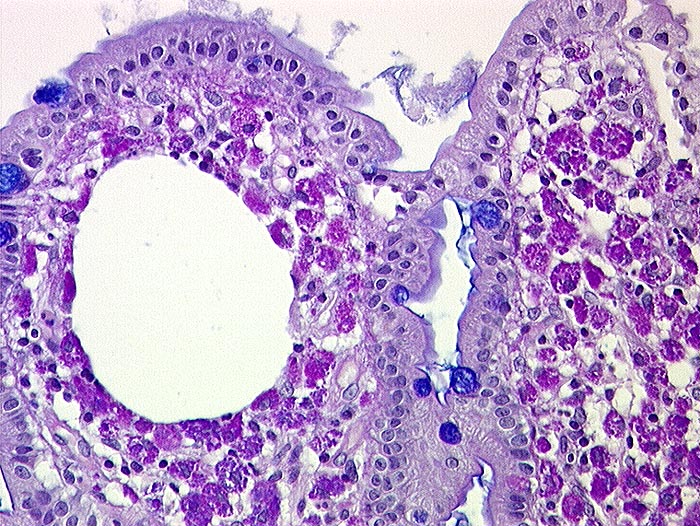

AP/ Morbus Whipple

Morbus Whipple

Entzündung infektiös

Dünndarm

Pathologischer Befund